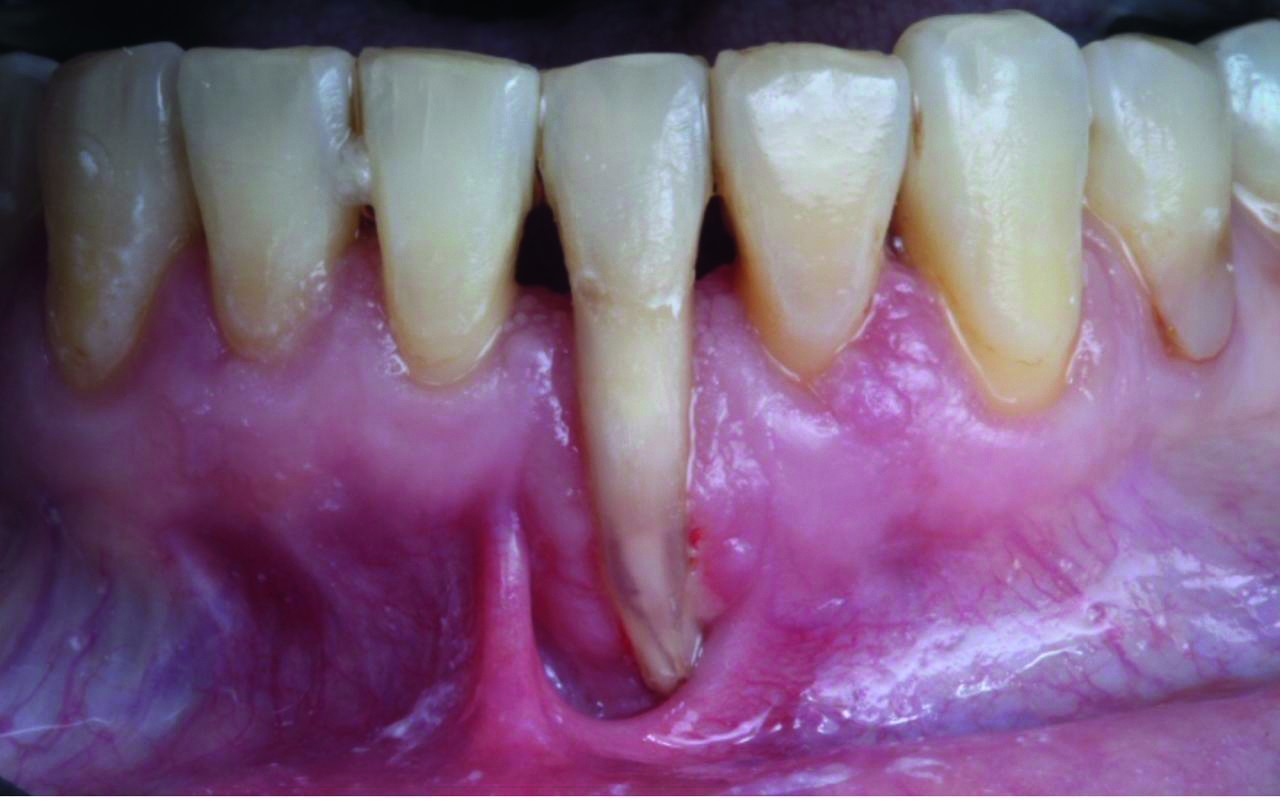

• Рецессии десны: причины и диагностика

• Устранение рецессий десны в области передних зубов нижней челюсти